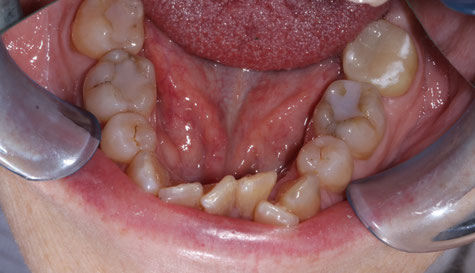

The photo above is an example of a severely undergrown arch in an adult.  This patient had 4 (permanent) premolars extracted, 4 wisdom teeth extracted  and orthodontic treatment in her youth to treat her severe crowding.  40 years later, this is what her teeth look like.